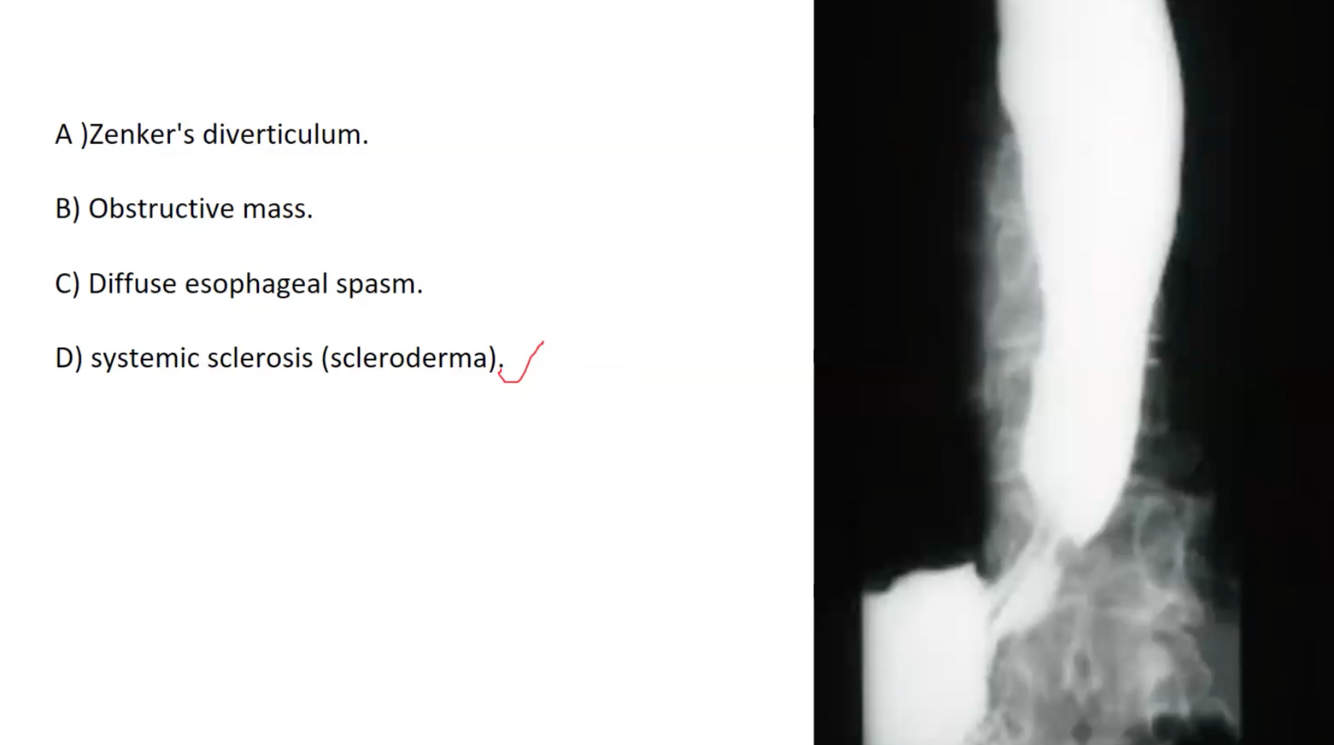

ESCLERODERMIA

DIFFUSE ESOPHAGEAL